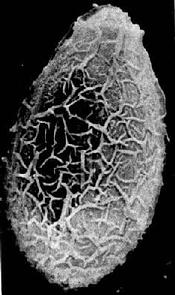

卵在近子宫前端已渐成熟,排出的卵呈黄褐色,内有成熟的毛蚴。卵甚小,平均为29×17µm,形状似芝麻,一端较窄且有盖,盖周围的卵壳增厚、形成肩峰,另一端有小疣状突起(图14-7、14-8)。

图14-8 华支睾吸虫卵扫描电镜图(许世锷供图)